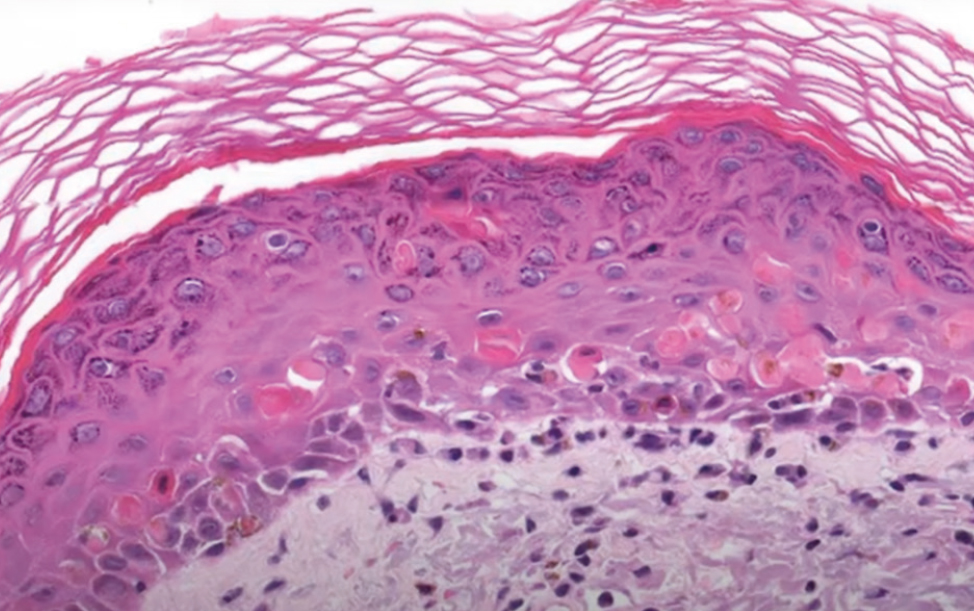

The histological study conducted on February 25, 2016, yielded the following conclusions (Fig. 6): There is lymphocytic infiltration at the dermoepidermal border, causing indistinctness of the basal layer due to immune cell destruction. Additionally, eosinophilic necrotic keratinocytes have been identified, and vesicular masses filled with lymphocytes have been observed.

Fig. 6. Histological findings.

Рис. 6. Гистологическая картина.